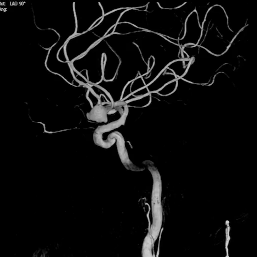

术前影像

CT及MRA:前交通动脉瘤。

造影显示:右侧Acom宽颈动脉瘤,大小约为7.5mm×10.5mm,动脉瘤底有双侧凸起,动脉瘤瘤颈宽,双侧A2段自动脉瘤侧壁发出。右侧A2起始直径1.7mm,左侧A2段起始部直径1.4mm。BOT试验显示左侧A1段不显影。